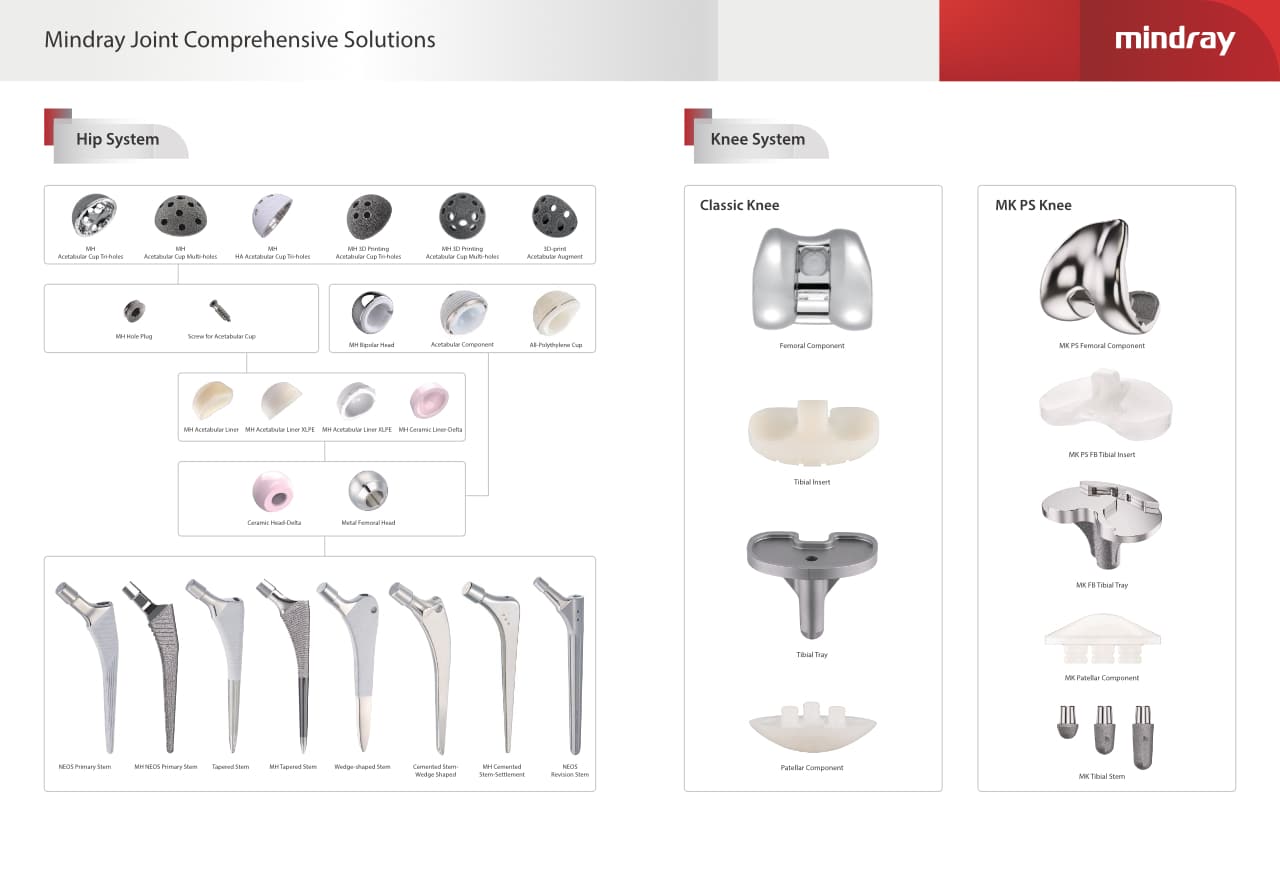

–Ю—А—В–Њ–њ–µ–і–Є—З–µ—Б–Ї–Њ–µ –њ–Њ–і—А–∞–Ј–і–µ–ї–µ–љ–Є–µ –Ї–Њ–Љ–њ–∞–љ–Є–Є Mindray, —А–∞—Б–њ–Њ–ї–Њ–ґ–µ–љ–љ–Њ–µ –≤ –£—Е–∞–љ–µ, —П–≤–ї—П–µ—В—Б—П –Њ–і–љ–Є–Љ –Є–Ј –≤–µ–і—Г—Й–Є—Е –њ—А–Њ–Є–Ј–≤–Њ–і–Є—В–µ–ї–µ–є –Њ—А—В–Њ–њ–µ–і–Є—З–µ—Б–Ї–Њ–є –њ—А–Њ–і—Г–Ї—Ж–Є–Є –Є–Ј –Ъ–Є—В–∞—П. –Ю–љ–Њ –Ј–∞–љ–Є–Љ–∞–µ—В—Б—П –Є—Б—Б–ї–µ–і–Њ–≤–∞–љ–Є—П–Љ–Є –Є —А–∞–Ј—А–∞–±–Њ—В–Ї–Њ–є, –њ—А–Њ–Є–Ј–≤–Њ–і—Б—В–≤–Њ–Љ –Є –Љ–∞—А–Ї–µ—В–Є–љ–≥–Њ–Љ —В—А–∞–≤–Љ–∞—В–Њ–ї–Њ–≥–Є—З–µ—Б–Ї–Є—Е –Є —Б–њ–Є–љ–∞–ї—М–љ—Л—Е –Є–Ј–і–µ–ї–Є–є, –њ—А–Њ–і—Г–Ї—Ж–Є–Є –і–ї—П –∞—А—В—А–Њ–њ–ї–∞—Б—В–Є–Ї–Є –Є –і—А—Г–≥–Є—Е —Е–Є—А—Г—А–≥–Є—З–µ—Б–Ї–Є—Е –Є–Ј–і–µ–ї–Є–є. –° –Љ–Њ–Љ–µ–љ—В–∞ —Б–≤–Њ–µ–≥–Њ –Њ—Б–љ–Њ–≤–∞–љ–Є—П –≤ 1999 –≥–Њ–і—Г –Љ—Л —Г—Б–њ–µ—И–љ–Њ –њ—А–Њ—И–ї–Є —Б–µ—А—В–Є—Д–Є–Ї–∞—Ж–Є—О ISO 9001, ISO 13485 –Є CE, –≤—Л–і–∞–љ–љ—Г—О T?V –Є —Н–Ї—Б–њ–Њ—А—В–Є—А—Г–µ–Љ –њ—А–Њ–і—Г–Ї—Ж–Є—О –≤ –±–Њ–ї–µ–µ —З–µ–Љ 50 —Б—В—А–∞–љ –њ–Њ –≤—Б–µ–Љ—Г –Љ–Є—А—Г.